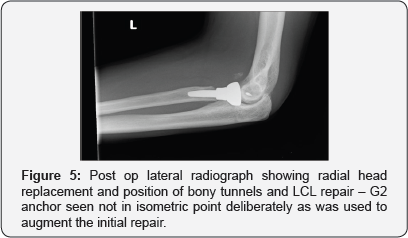

The radial head was more comminuted than expected from the preoperative imaging and was not salvageable and was therefore excised using a reciprocating saw and the articular cartilage removed to be use as a source of bone graft. A separate small dorsal incision using an ACL guide was used to drill two bone tunnels through the ulna to allow for a suture lasso technique to be used to capture the brachial is and a small bony fragment of the coronoid. Sutures were passed but not tied until the radial head had been replaced using an uncemented prosthesis (Acumed Anatomic radial head system) and bony tunnels in the lateral epicondyle drilled and sutures passed to allow for a Krakow type repair of the lateral collateral ligament complex (LCL) as described by the Mayo group. At the end of the procedure following radial head replacement, coronoid fixation and LCL reconstruction intraoperative stability was assessed. The elbow was stable to full flexion and to within 20 degrees short of full extension with gentle pressure and therefore a separate medial incision was not felt to be needed to address the medial structures and the repair was protected with a hinged elbow brace to allow a graduated return to full extension.

His check radiographs at 3 months show that the distal radius has gone on to unite well and that his elbow remains in joint. (Figures 5 & 6) At 6 month follow up he is back to his recreational activities and his elbow range of motion documents full pronation and supination, full flexion to 160 degrees and he lacks the terminal 10 degrees of extension and had a “functional arc” range of 150 degrees.